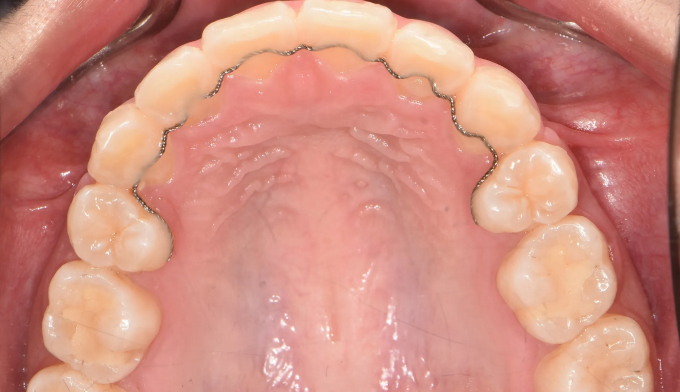

덧니

덧니가 있고, 입도 약간의 돌출감을 보입니다. 발치교정을 통해 이 모두를 해소할 수 있습니다.

치료도중, 환자 본인이 입이 너무 들어가서 얼굴 형태가 급격히 바뀌는것을 걱정하여 입을 최소한으로 집어넣기로 하였습니다. 따라서 발치 공간은 모두 치열을 가지런하는데 이용하기로 하였습니다.

발치후 교정하게 되면 교정을 위한 공간이 충분하므로 입의 전후방 위치를 마음껏 조정할 수 있다는 장점이 있습니다. 교정 중 입술의 모양이나 돌출정도를 바꾸고 싶다면 주치의에게 언제든 말씀해주세요!

교정기간은 20개월 소요되었습니다.